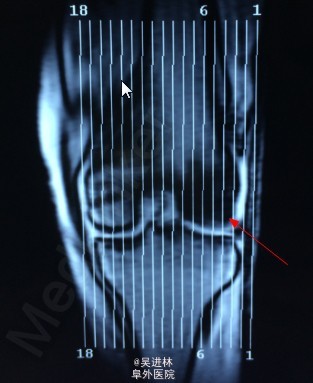

患者6个月前无明显诱因出现左膝关节内侧间隙疼痛,就诊于当地医院,诊断为骨坏死(骨髓水肿易误诊为骨坏死),行左股骨内侧髁开窗病灶清除术。一月前无明显诱因再次出现左膝关节外侧间隙疼痛,无法行走,站立及上下楼梯,无发热,无腰痛,无下肢肿胀,我院诊断为“骨髓水肿”。骨髓水肿发生于单髁是比较少见的,通常累及整块骨头,这个病人不仅在单髁发生骨髓水肿,而且奇怪的是,左侧髁水肿好了之后,外侧髁侧又出现了水肿。